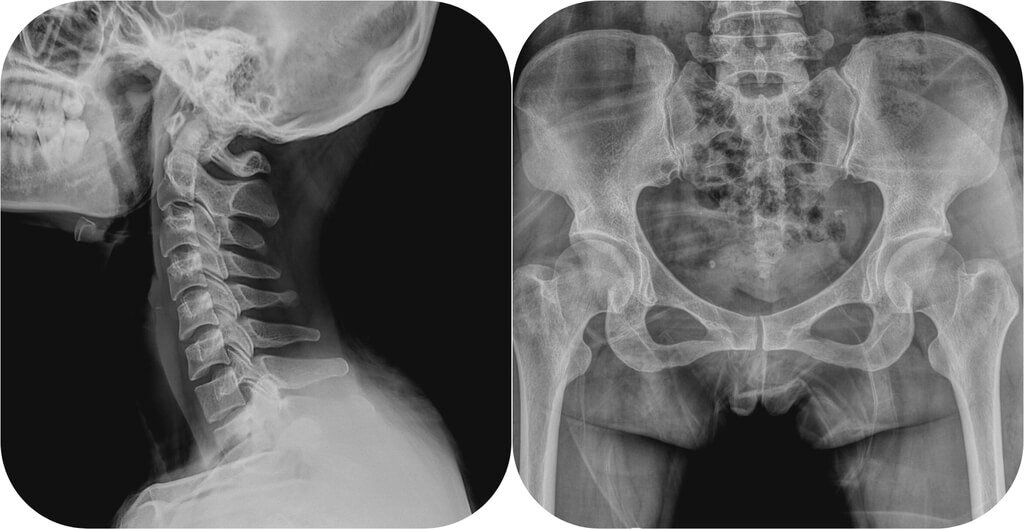

Рентгенография – основной метод рентгенологического исследования, который заключается в получении рентгенограммы: теневого изображения органов на рентгеновской пленке.

На рентгеновском снимке врач видит тени разной интенсивности: на месте костей – белые участки, на месте мягких тканей – серые; легкие на рентгенограмме выглядят черными. Рентгеновские снимки получаются контрастными, так как разные ткани по-разному улавливают рентгеновские лучи: чем плотнее ткань, тем более светлой она будет на рентгеновском изображении.

Рентгенограммы по своей сути являются негативами, поэтому более светлые участки на них называются затемнениями. К примеру, плотный и светлый участок воспаления легких на фоне «темных» воздушных легких обозначается врачом как тень. Перелом кости будет виден как более темный «разлом» на светлом «поле» кости.

Теневые изображения, полученные методом рентгенографии, дают врачу информацию о состоянии различных органов (легкие, сердце, желудок, лимфоузлы, кости, позвоночник и пр.), а также позволяют выявить разные патологии: участки воспаления, деструкции (разрушения), дистрофии, опухолевые узлы, аномалии развития органов.